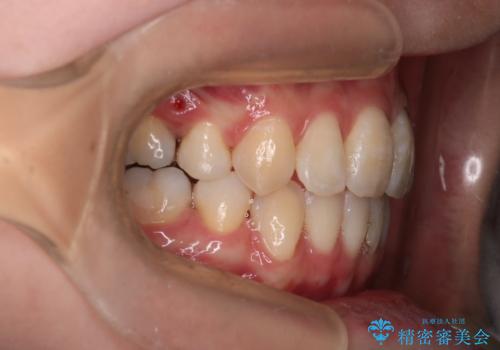

- 出っぱによる口元の閉じにくさを主訴に来院されました。上顎の出っ歯と上下顎叢生も認められたため、上下顎両側4番抜歯を行い、ワイヤー矯正で治療する治療計画を立てました。

上顎にはMI(マイクロインプラント)を埋入して固定源とすることで出っ歯の改善を図りました。

少しスペースクローズに時間がかかりましたが、MIを用いたワイヤー矯正で

主訴である出っ歯と叢生が改善されました。口も閉じやすくなり、スッキリとした口元になりました。